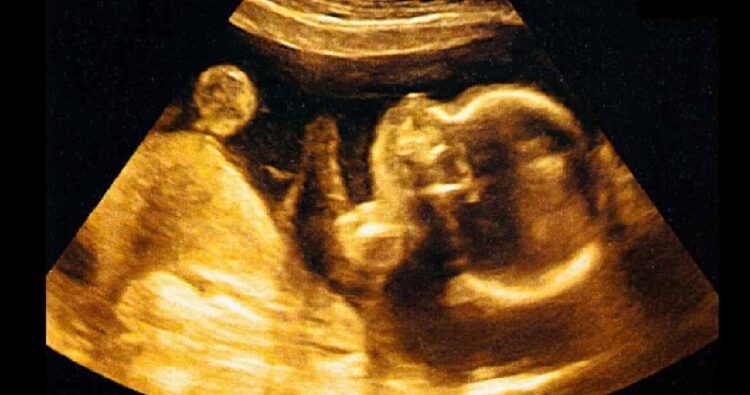

ലക്നൗ : വീടിന്റെ ടോയ്ലറ്റ് പൈപ്പിൽ ആറ് മാസം പ്രായമുള്ള ഭ്രൂണം കുടുങ്ങിയതായി റിപ്പോർട്ട്. വീടിന്റെ ഉടമ ദേവ എന്ന ദേവേന്ദ്രയാണ് പൈപ്പ് പൊട്ടിച്ച് ഭ്രൂണം പുറത്തെടുത്തത്. വിവരമറിഞ്ഞ് ഇന്ദിരാപുരം പോലീസ് സ്ഥലത്തെത്തി സ്ഥലമുടമയെ ചോദ്യം ചെയ്തപ്പോൾ രാവിലെ ശുചിമുറിയിൽ വെള്ളം കെട്ടി നിന്നതായും പൈപ്പ് മുറിച്ചപ്പോൾ പൈപ്പിൽ ഭ്രൂണം കുടുങ്ങി നിൽക്കുന്നത് കണ്ടതായും ദേവ പറഞ്ഞു. തന്റെ വീട്ടിൽ 9 വാടകക്കാർ താമസിക്കുന്നുണ്ടെന്നും ഇയാൾ പോലീസിനോട് പറഞ്ഞു.

ഭ്രൂണത്തിന്റെ ഡി എൻ എ പരിശോധന നടത്തുമെന്ന് ഇന്ദിരാപുരം അസിസ്റ്റൻ്റ് പോലീസ് കമ്മീഷണര് സ്വതന്ത്ര കുമാര് സിംഗ് പറഞ്ഞു.സംഭവം നാട്ടുകാരിൽ ആശങ്കയുണ്ടാക്കിയിട്ടുണ്ട്. അതേസമയം കേസിൽ അന്വേഷണം ആരംഭിച്ചതായി പൊലീസ് പറഞ്ഞു.